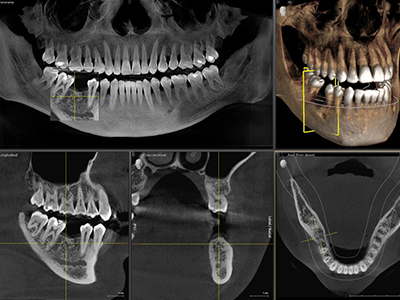

CT

通常のX線ではわかりづらい根管治療や移植への対応、歯周病など3次元での診断が可能となり、より安全で正確な治療を施すことができます。

また矯正診断、気道解析もできます。